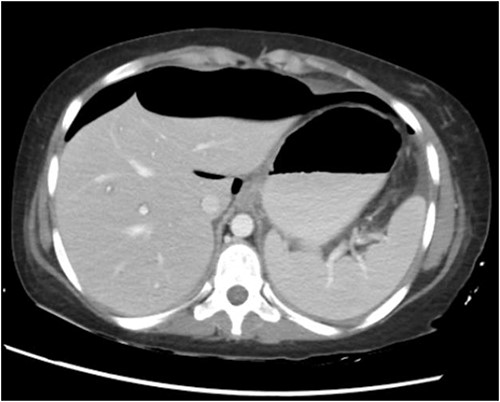

CT abdomen with oral and intravenous contrast was done, which revealed gross pneumoperitoneum, significantly dilated stomach with dilated multiple small bowels loops up to the distal ileum with no evidence of contrast extravasation. Moderate ascites with mesenteric congestion were seen (Fig. 2).

She was seen in the clinic 1 week later with a repeat CT scan. She had complete resolution of her symptoms and the imaging showed interval resolution of previously noted gross pneumoperitoneum.